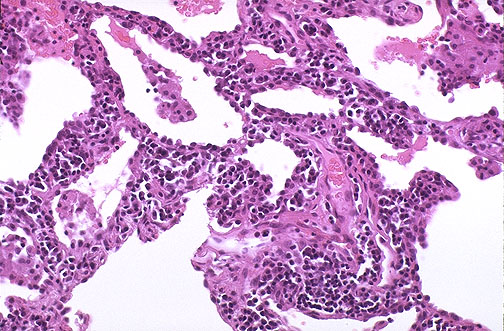

| This is an example of lymphocytic interstitial pneumonitis (LIP) in which small lymphocytes fill the interstitium and perivascular regions of the lung. This disease appears uncommonly in adults with autoimmune diseases. It is uncommon in children except in the setting of AIDS. |